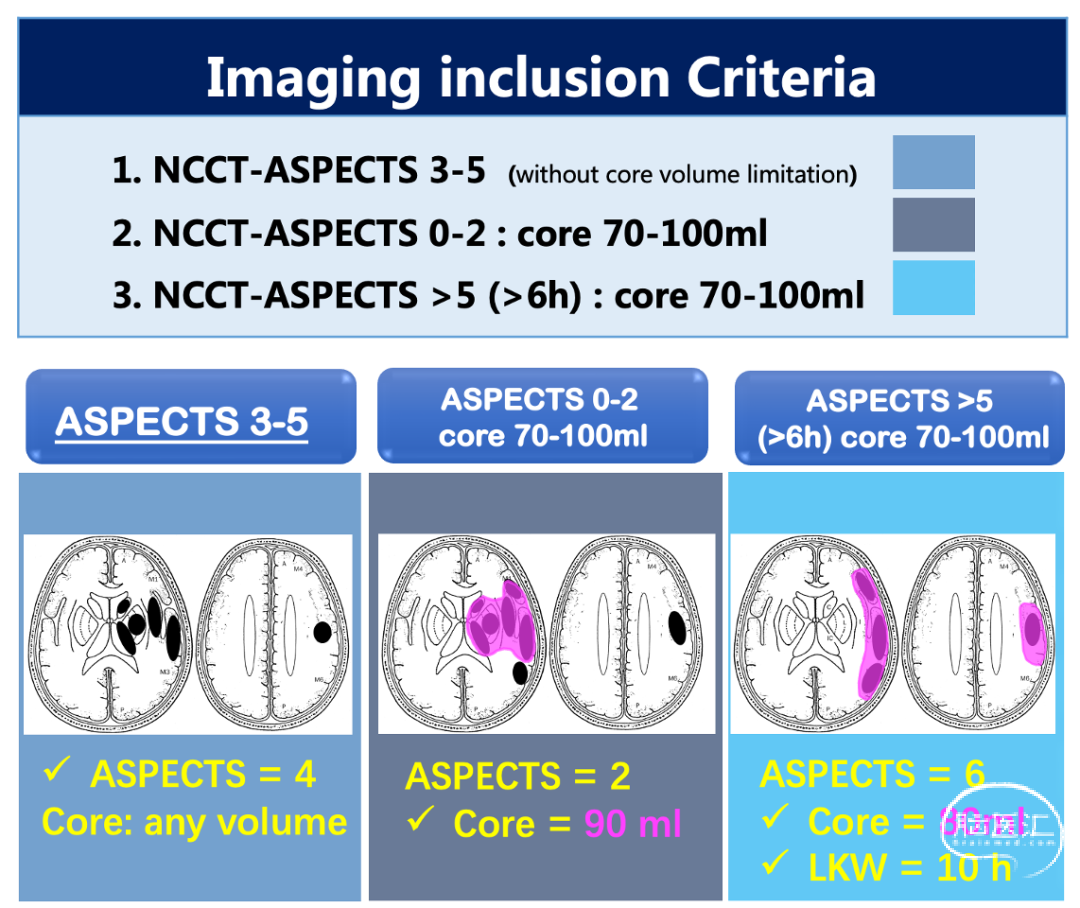

对于入组的影像,ANGEL-ASPECT研究的目的是纳入对多的潜在获益的大核心梗死人群。因此,对于大核心梗死常用的两种定义——ASPECTS评分和核心梗死体积,该项目均进行了入组的影像设定。结合以往研究提示的大核心梗死潜在获益范畴,ANGEL-ASPECT研究对于ASPECTS评分和梗死体积都做了上限的界定。整体的标准就是“ASPECTS低,但不是特别低;核心梗死大,但不能特别大。”符合任何一种可能获益的大核心梗死范畴时,也均可纳入。因此,研究设计上在不违背现有指南最高级别推荐的前提下,对指南中推荐级别较低的病人进行随机对照研究。

影像的入排标准如下:

1)发病24h内,平扫CT的ASPECTS评分为3-5分:全部纳入研究,不考虑核心梗死体积的上下限;

2)发病24h内,平扫CT的ASPECTS评分为0-2分,但梗死体积在70ml-100ml:鉴于梗死体积未超过100ml,具有潜在获益性,可以纳入研究;

3)发病6-24h,平扫CT的ASPECTS评分大于5分,体积在70ml-100ml:该部分人群的体积超过现有指南中体积(DAWN和DEFUSE 3),可以纳入研究。